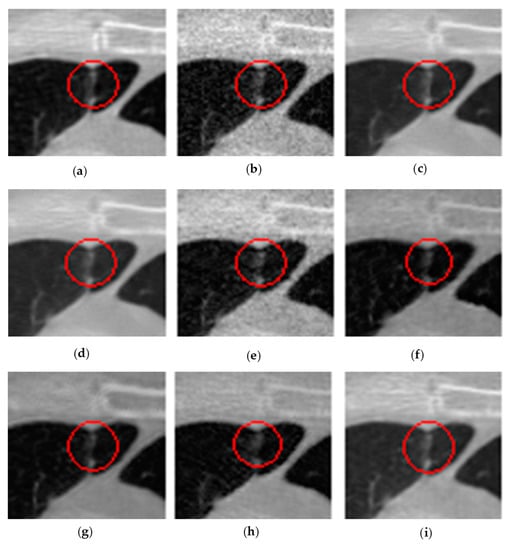

3.5. Results and Analysis